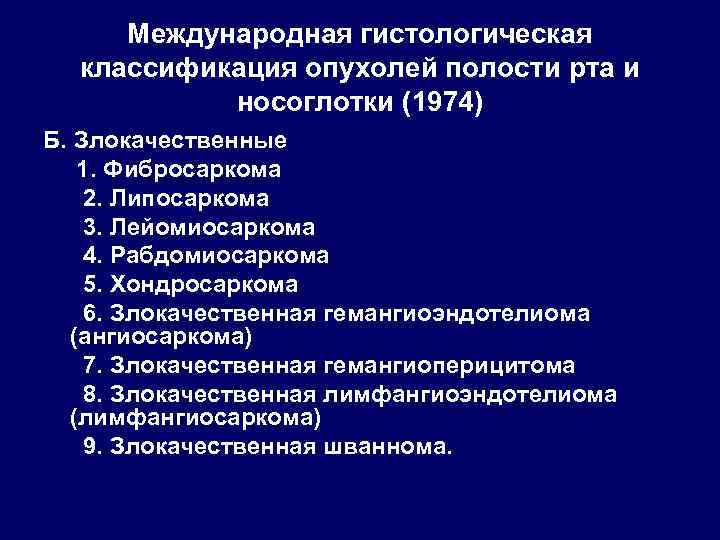

Международная гистологическая классификация опухолей полости рта и носоглотки (1974) Б. Злокачественные 1. Фибросаркома 2. Липосаркома 3. Лейомиосаркома 4. Рабдомиосаркома 5. Хондросаркома 6. Злокачественная гемангиоэндотелиома (ангиосаркома) 7. Злокачественная гемангиоперицитома 8. Злокачественная лимфангиоэндотелиома (лимфангиосаркома) 9. Злокачественная шваннома.

Международная гистологическая классификация опухолей полости рта и носоглотки (1974) Б. Злокачественные 1. Фибросаркома 2. Липосаркома 3. Лейомиосаркома 4. Рабдомиосаркома 5. Хондросаркома 6. Злокачественная гемангиоэндотелиома (ангиосаркома) 7. Злокачественная гемангиоперицитома 8. Злокачественная лимфангиоэндотелиома (лимфангиосаркома) 9. Злокачественная шваннома.